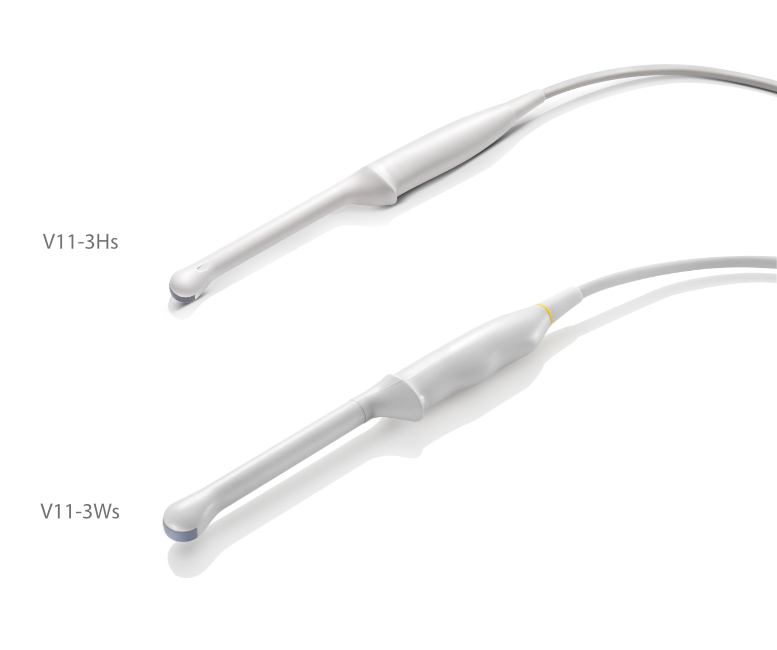

Transducers